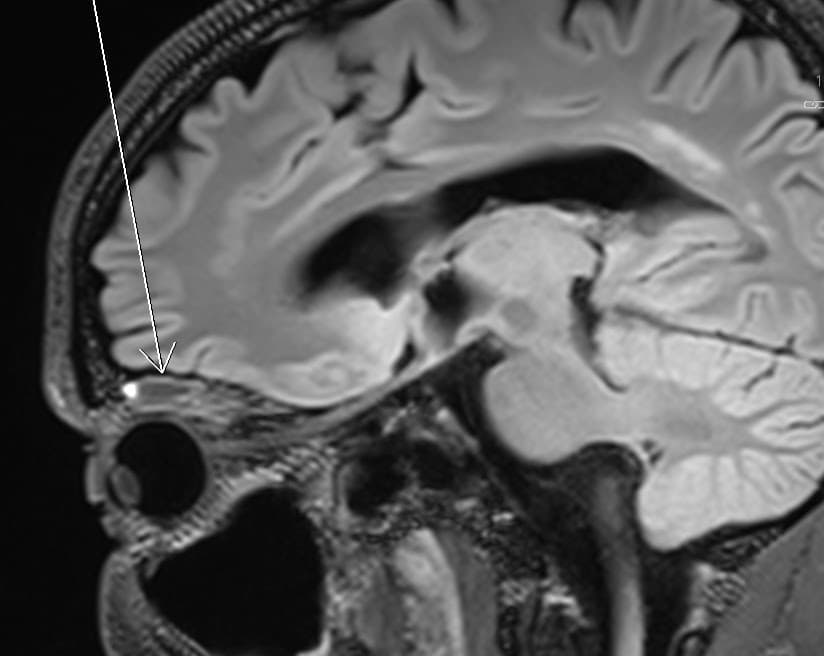

En 55-årig mand blev henvist til øjenafdelingen med ptose og inferior displacering af højre øje (A og B). Patienten, der var erfaren fridykker, havde to uger inden måttet afbryde et dyk på 12 meters dybde grundet problemer med trykudligning. Straks efter dykket bemærkede dykkermakkeren en ændring ved højre øje. I dagene efter tilkom periokulært hæmatom og dobbeltsyn. Ved objektiv undersøgelse fandtes højre øje displaceret nedad med indskrænket elevation. MR-skanning viste subperiostalt orbitalt hæmatom (SOH) i orbitaloftet (C).

SOH er en sjælden tilstand, der opstår ved blødning fra vener i hulrummet mellem knogle og det løst nedbundne periostium i orbita. SOH opstår oftest ved traumer eller venøs trykstigning, f.eks. i forbindelse med opkastninger, fødsler, vægtløftning og strangulation [1]. SOH opstået i forbindelse med dykning kan opstå som et barotraume fra manglende trykudligning af luftvoluminet i dykkermasken. Luft i masken komprimeres ved neddykning og skaber et undertryk, der påvirker bløddelene i orbita, populært kaldet et »mask squeeze« [2].